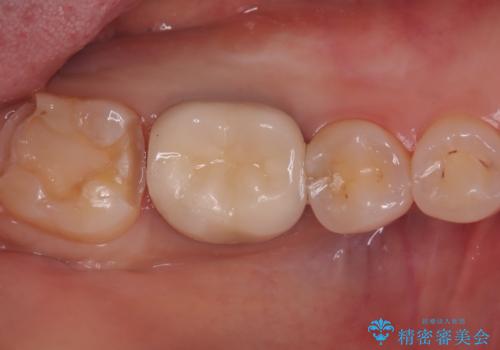

クリーニングにいらした患者さんで、右下7番目の歯の奥側の面や手前の歯との間にう蝕があり、噛む面にも蝕処置によるレジン材料が詰まっていたことから、う蝕も古い材料も全て除去しセラミックインレーでのやり替えとなりました。

右下7近遠心にカリエスを認め、咬合面のCR修復も劣化していたので、カリエスと古い材料を全て除去し新しくCR裏層した後、セラミックインレーをセットしています。セット時はラバーダム防湿を行っています。